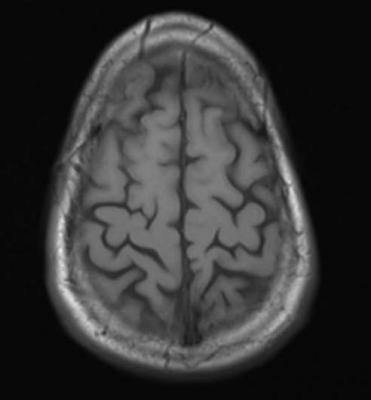

May 19, 2015 — New study results show a simple blood test to measure brain-specific proteins released after a person suffers a traumatic brain injury (TBI) can reliably predict both evidence of TBI on radiographic imaging and injury severity. The potential benefit of adding detection of glial fibrillary acidic protein breakdown products (GFAP-BDP) to clinical screening with computed tomography (CT) and magnetic resonance imaging (MRI) is described in an article published in Journal of Neurotrauma.

Paul McMahon of the University of Pittsburgh Medical Center, and a team of international researchers, including TRACK-TBI investigators, analyzed blood levels of GFAP-BDP from patients ages 16-93 years treated at multiple trauma centers for suspected TBI. They evaluated the ability of the blood-based biomarker to predict intracranial injury as compared to the findings on an admission CT and a delayed MRI scan. The authors reported a net benefit for the use of GFAP-BDP above imaging-based screening alone and a net reduction in unnecessary scans by 12-30 percent in the article "Measurement of the Glial Fibrillary Acidic Protein and Its Breakdown Products GFAP-BDP Biomarker for the Detection of Traumatic Brain Injury Compared to Computed Tomography and Magnetic Resonance Imaging.”